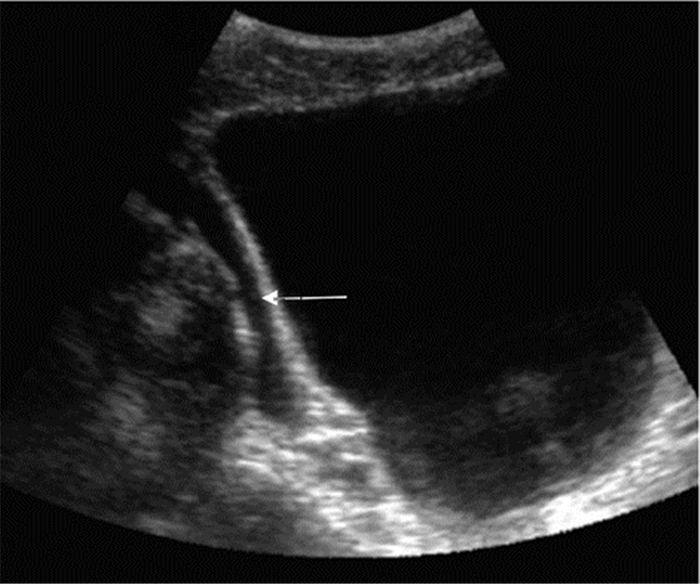

3.1.3 创伤的超声诊断的步骤及流程(1)创伤的超声诊断步骤:创伤患者床旁超声检查至少5个部位:①右上腹,也叫肝周切面、莫里森窝切面或右上1/4切面。如出现无回声区提示腹腔内出血(图 22-23)。②左上腹脾肾间隙,如出现无回声区亦提示腹腔内出血(图 24-25);③耻骨上/盆腔切面,如显示膀胱后或子宫后无回声区,提示盆腔出血可能(图 26-27);④剑突下切面,常用于探查心包有无无回声区(图 28),具体心包积液征象见2.1.2 常见异常超声心动声像图。⑤肺部超声,主要用于探查有无血气胸、肋骨骨折,具体征象见2.2肺超声。

| 图 24 脾肾间隙部位及正常超声影像 |

| 图 25 脾肾间隙出现无回声区 |